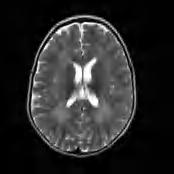

Zespół delecji 18q(–) jest związany z brakiem podstawowego białka mieliny (MBP, myelin basic protein), dla którego gen znajduje się w końcowym odcinku długiego ramienia chromosomu 18. Obraz kliniczny jest różny w zależności od wielkości delecji i związanego z tym ubytku materiału genetycznego. Najczęściej obserwuje się opóźnienie rozwoju psychoruchowego, wiotkość lub niezgrabność ruchową, małogłowie, niekiedy różne cechy dysmorficzne twarzoczaszki, w tym uszu (łącznie z zarośnięciem przewodu słuchowego i/lub niedosłuchem bądź głuchotą), niekiedy wady serca, rzadziej wady kończyn i narządów płciowych. W cięższych postaciach obserwuje się oczopląs, ataksję, zespół pozapiramidowo-pozapiramidowy. W najłagodniejszych postaciach występują jedynie wiotkość i niewielka niezgrabność ruchowa, rozwój umysłowy może mieścić się w granicach tzw. szerokiej normy. Dopiero badanie RM wykonane z innych powodów może ujawnić upośledzoną mielinizację. Stężenie białka w płynie mózgowo-rdzeniowym jest prawidłowe. Obraz RM mózgu charakteryzuje się słabym zróżnicowaniem sygnału kory i istoty białej z nieostro odgraniczonymi ogniskami o różnej intensywności sygnału, niekiedy „jakby rozmytymi” w sekwencjach T2-zależnych, FLAIR oraz T1-zależnych (ryc. 5.4); może występować zanik móżdżku. W diagnostyce niezbędne są badania genetyczne – analiza chromosomów metodą porównawczej hybrydyzacji genomowej (aCGH).

Rycina 5.4. Zespół delecji 18q(–). RM mózgu charakteryzuje się słabym zróżnicowaniem sygnału kory i istoty białej z nieostro odgraniczonymi ogniskami o różnej intensywności sygnału, niekiedy „jakby rozmytymi” w sekwencjach T2-zależnych, FLAIR oraz T1-zależnych.